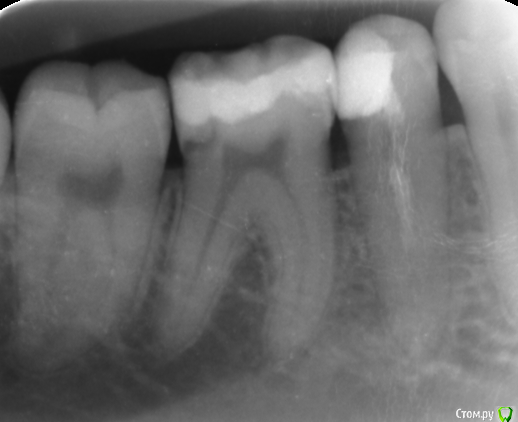

OlgaVeva Опубликовано 15 января, 2019 Поделиться Опубликовано 15 января, 2019 Здравствуйте! Ситуация такая: месяц назад мне запломбировали зуб, нижнюю шестерку справа. Через несколько дней я делала снимки соседнего зуба, и обнаружилось что-то темное в этом зубе (шестерке). Что это значит? Нужно все переделывать или это нормально? Там где темное, как раз была дырка, и ранее этот зуб уже пломбировался. Спасибо. Ссылка на комментарий

St. Опубликовано 15 января, 2019 Поделиться Опубликовано 15 января, 2019 Некоторые материалы могут быть неконтрастными, то есть черные на снимке Ссылка на комментарий